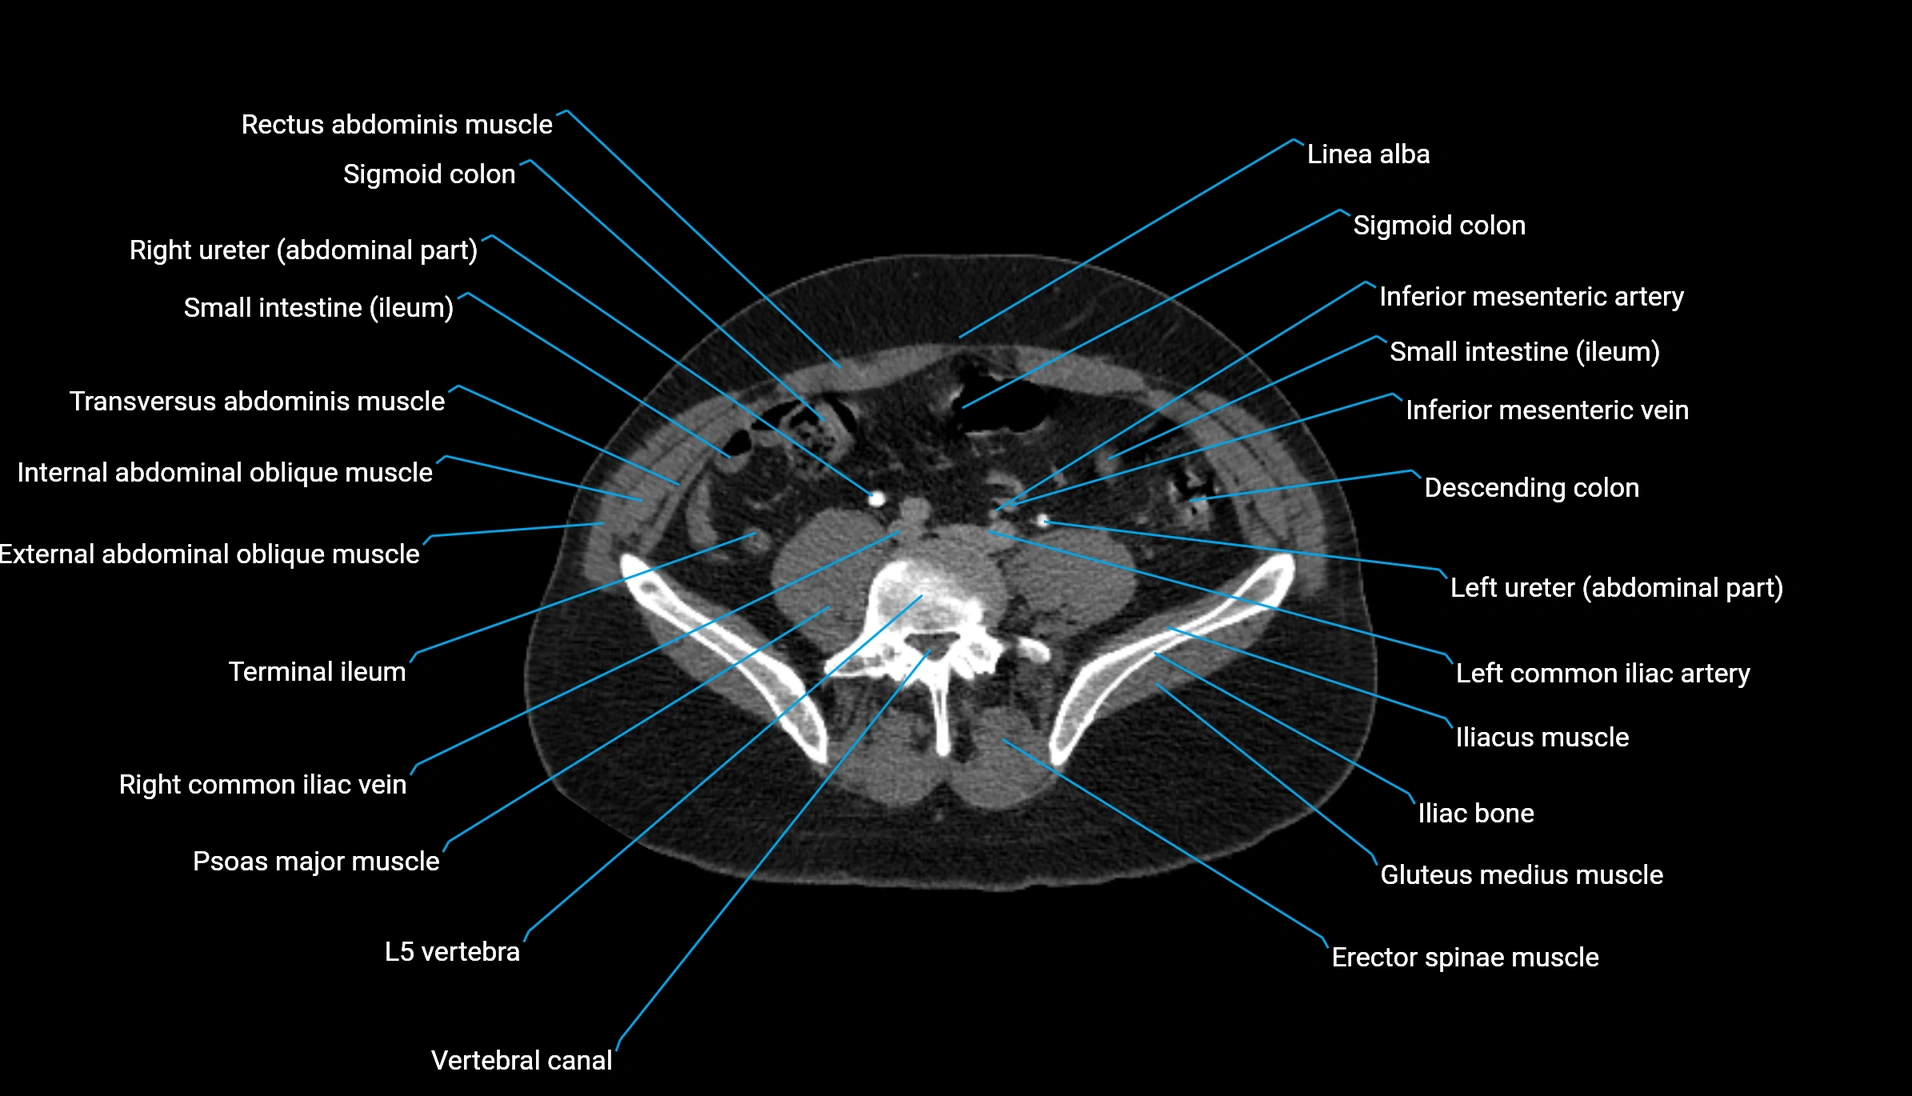

CT Appearance

Non-contrast CT:

-

Demonstrates cortical bone of acetabular rim in excellent detail

Detects fractures, dysplasia, retroversion, or bony overcoverage (pincer impingement)

3D reconstructions used in preoperative hip surgery planning

CT VRT 3D image

CT image